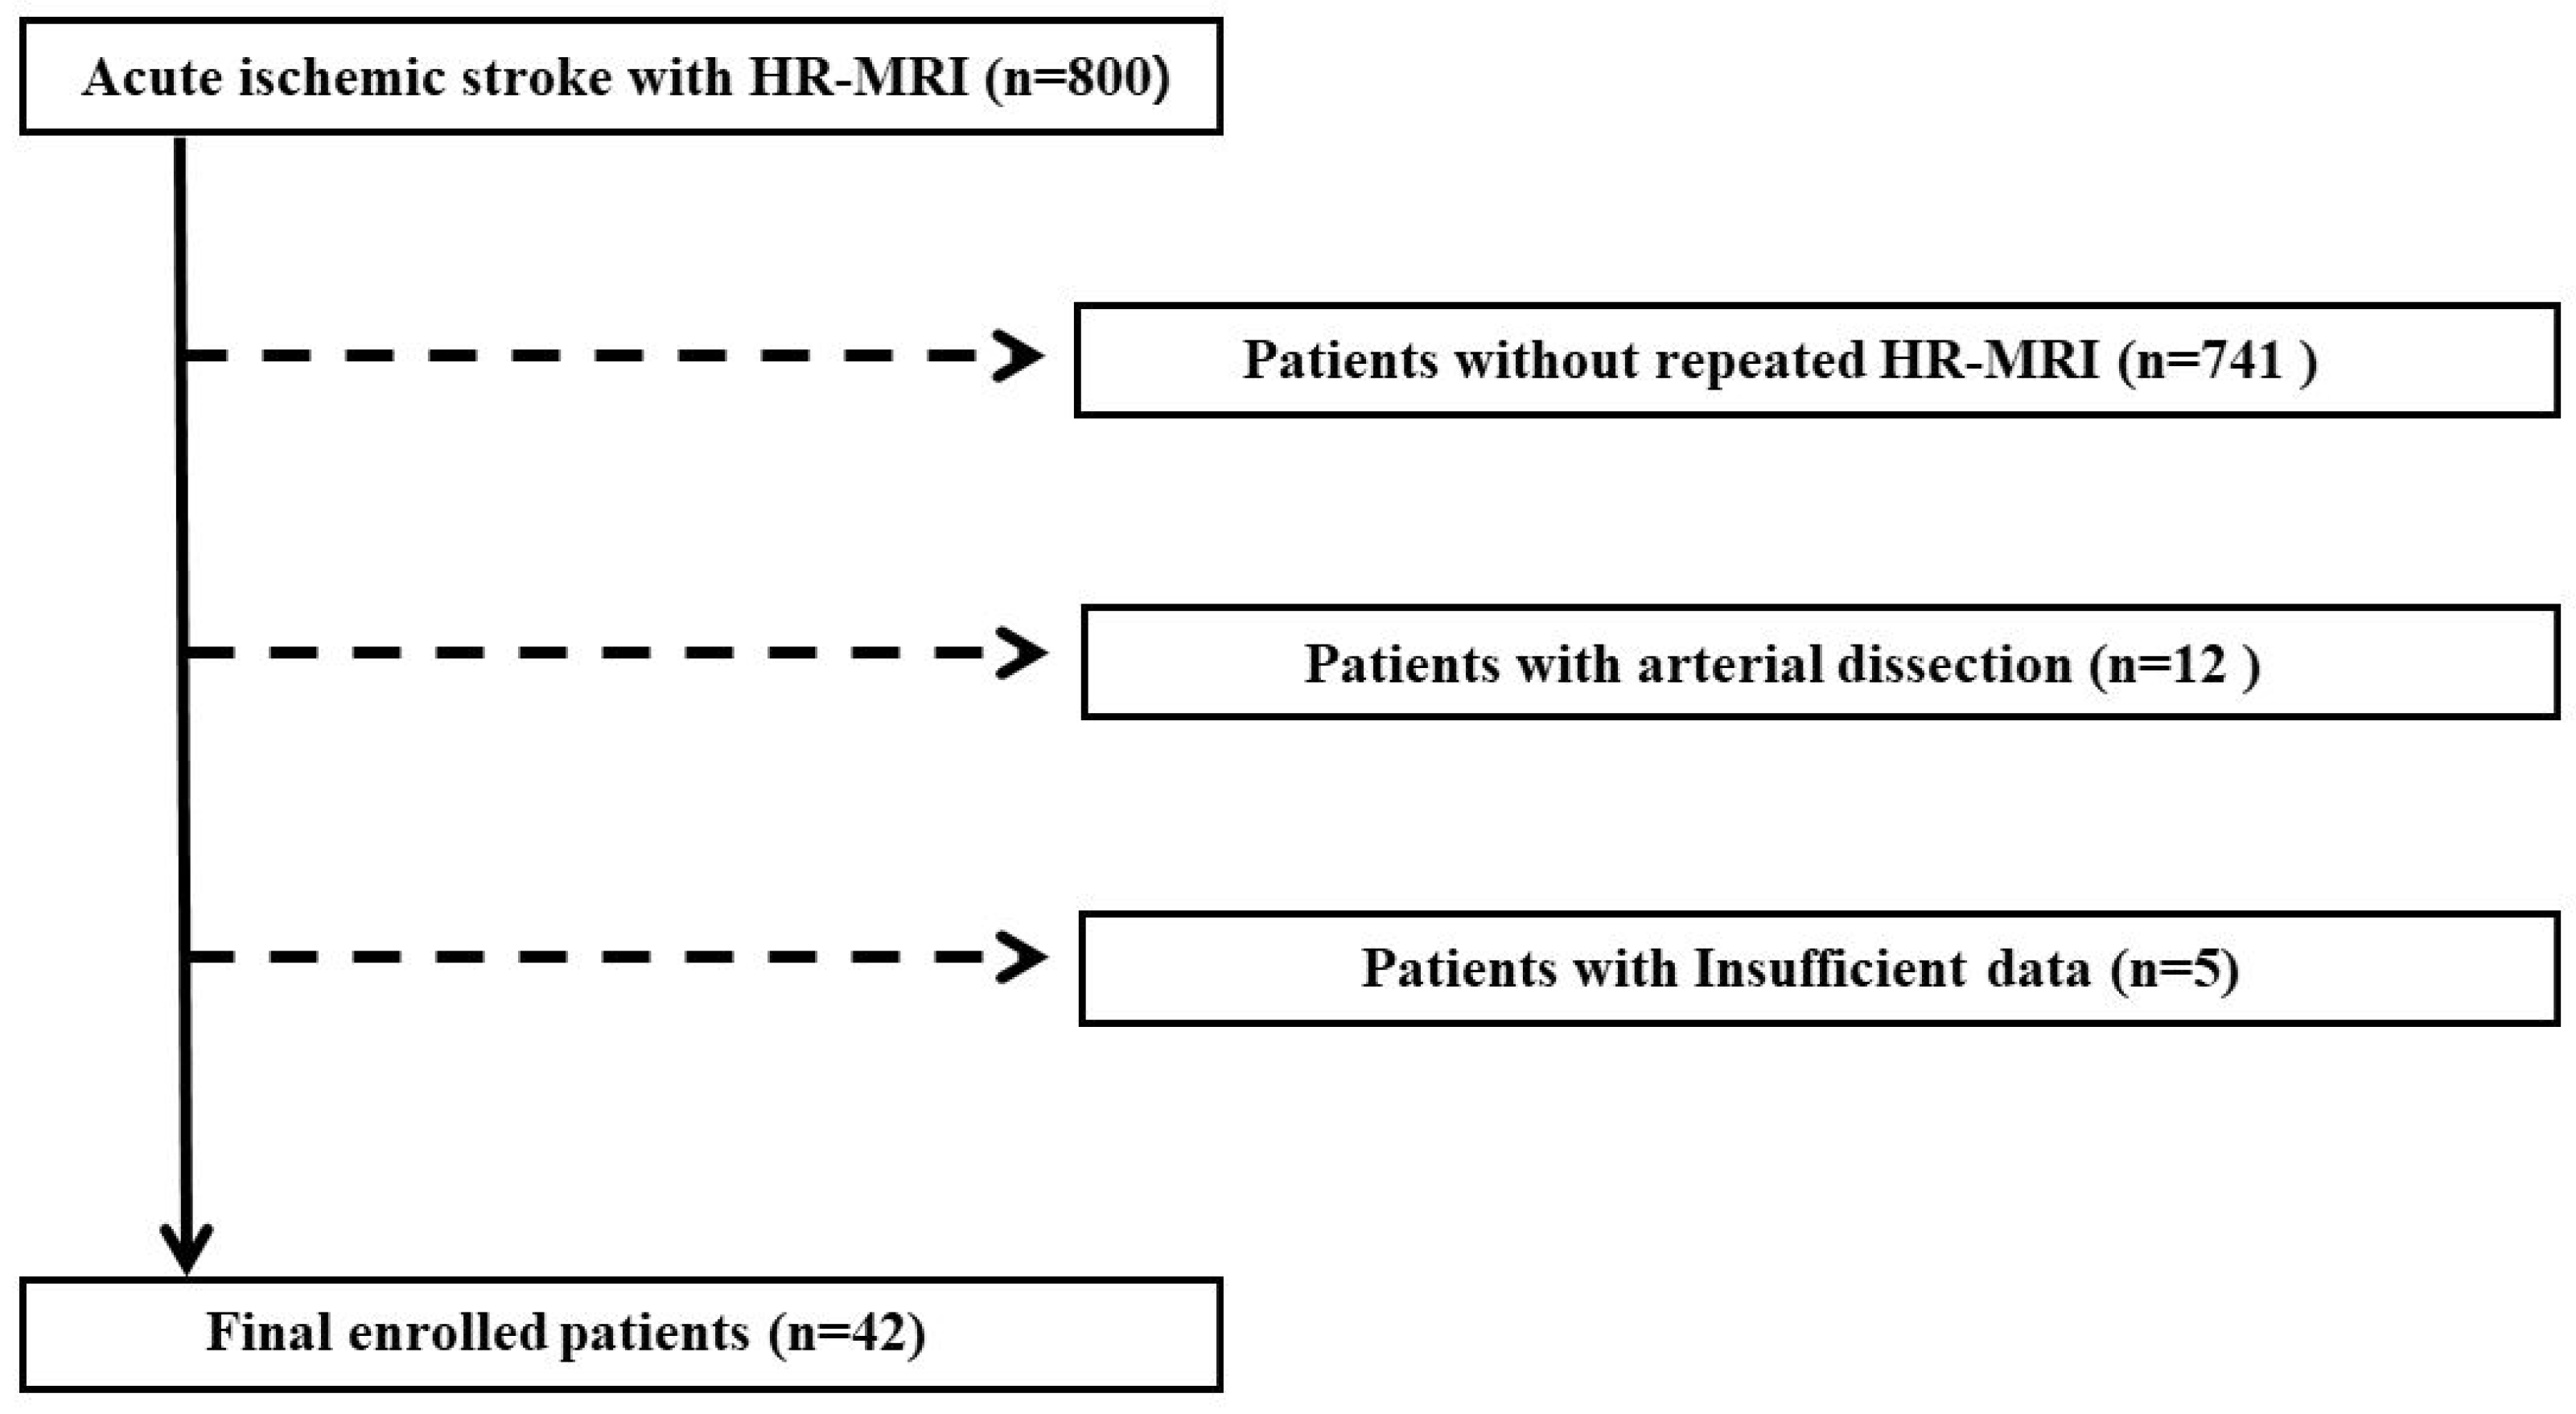

2. Materials and Methods

2.1. Study Population